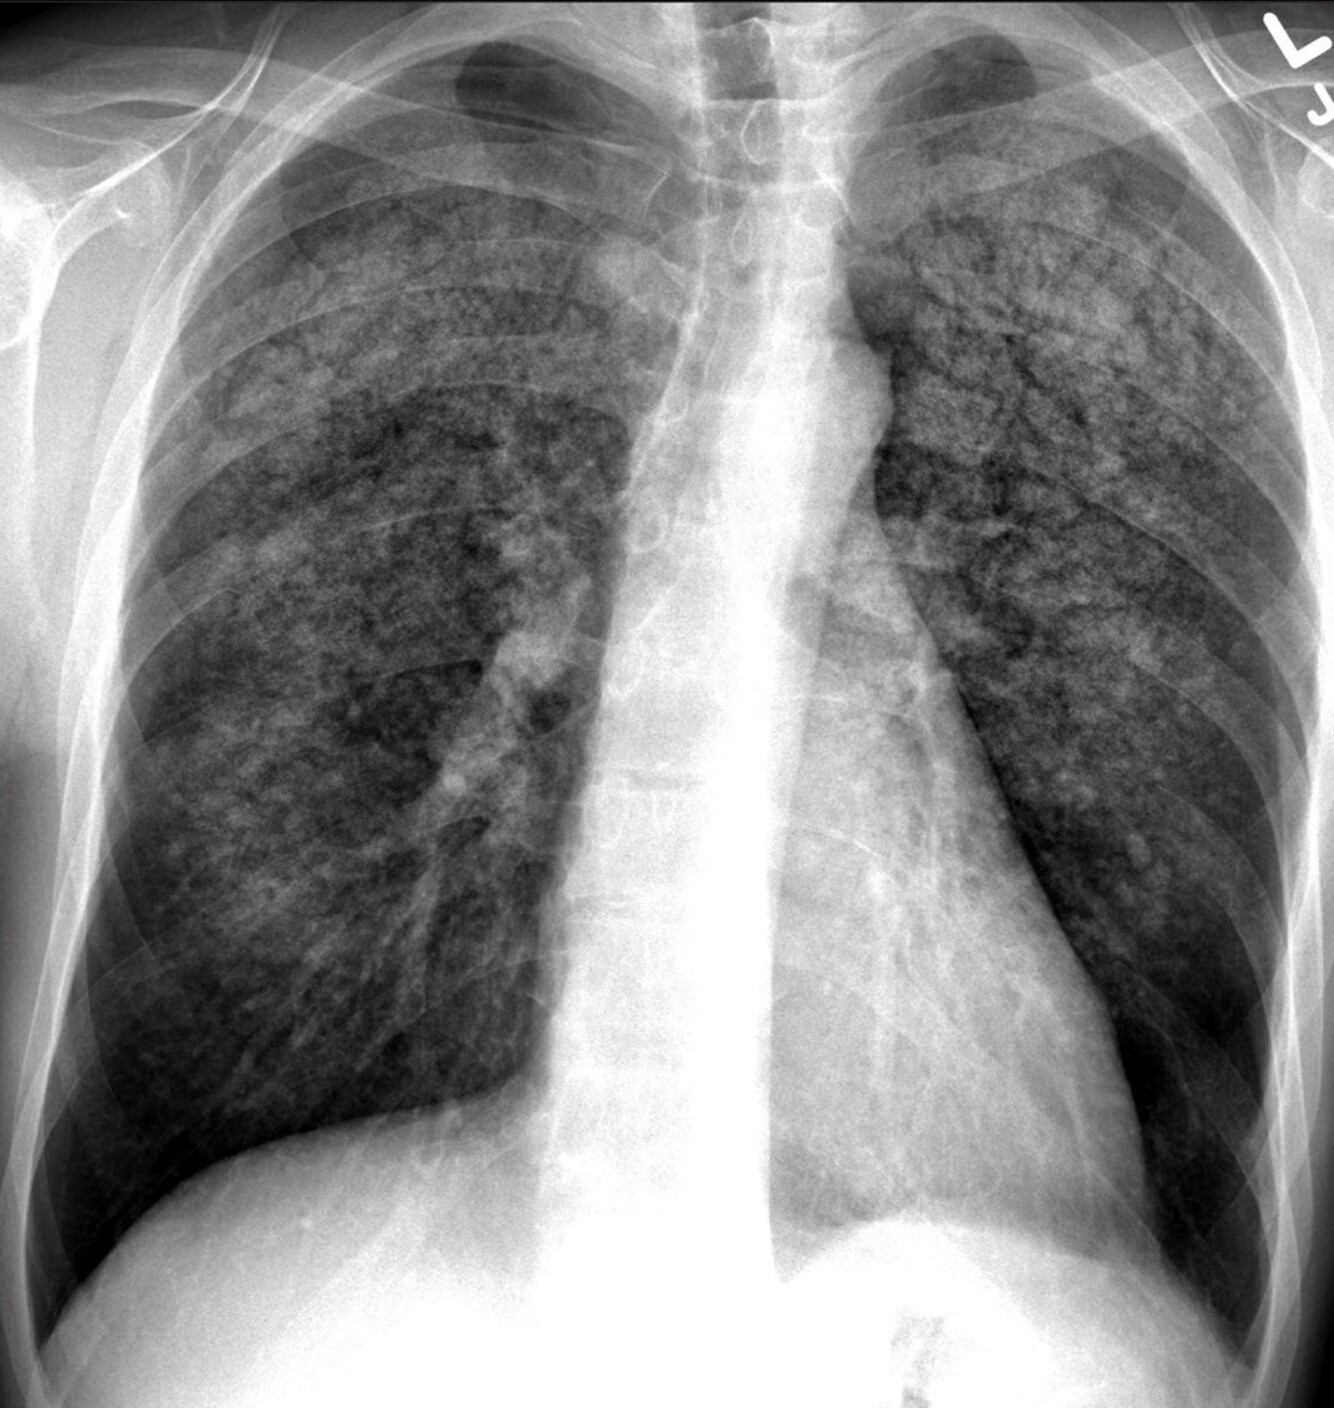

Metastatic calcification (ground glass opacities)

Patient has known renal failure, diabetic, chest pain, SOB, creatinine is high (indicates kidney poor kidney function) Shows ground glass opacities.

Metastatic calcifications

Chronic Renal Failure  Acts on bone and other tissue to release their calcium into the blood, which builds up in different organs. Abnormal bone metabolism high phosphorus and calcium

Metastatic calcification